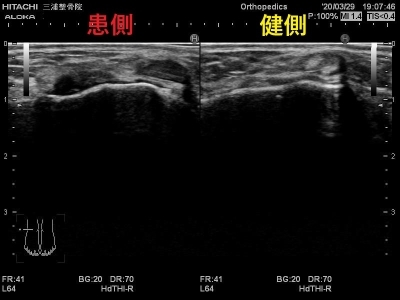

エコーではこのように写ります。

患側では大きく腫れて

正常な靭帯線維が見えないため

二分靭帯が断裂しています。